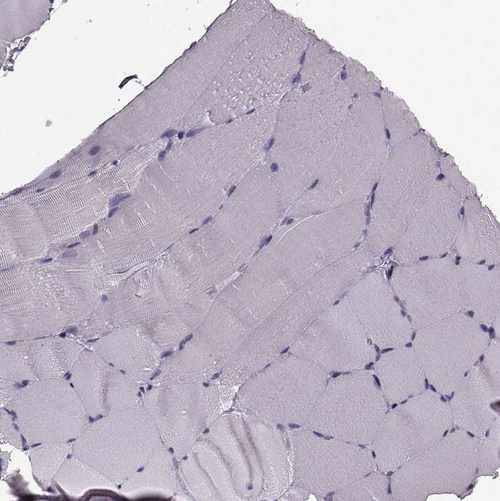

Immunohistochemistry analysis in human bone marrow and skeletal muscle tissues using HPA040442 antibody. Corresponding CST7 RNA-seq data are presented for the same tissues.